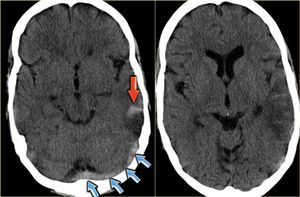

What is your diagnosis?

Epidural hemoragic

Any chance of venous thrombosis?

Epidural hematoma can cause lucid interval, hypertension and bradycardia but doesn't causes venous thrombosis as its bleeding from artery and is increasing pressure outside.

It is a concave shaped lesion which is due to artery rupture leading to EDH. I think so!

It is SDH and CVT (mixed)